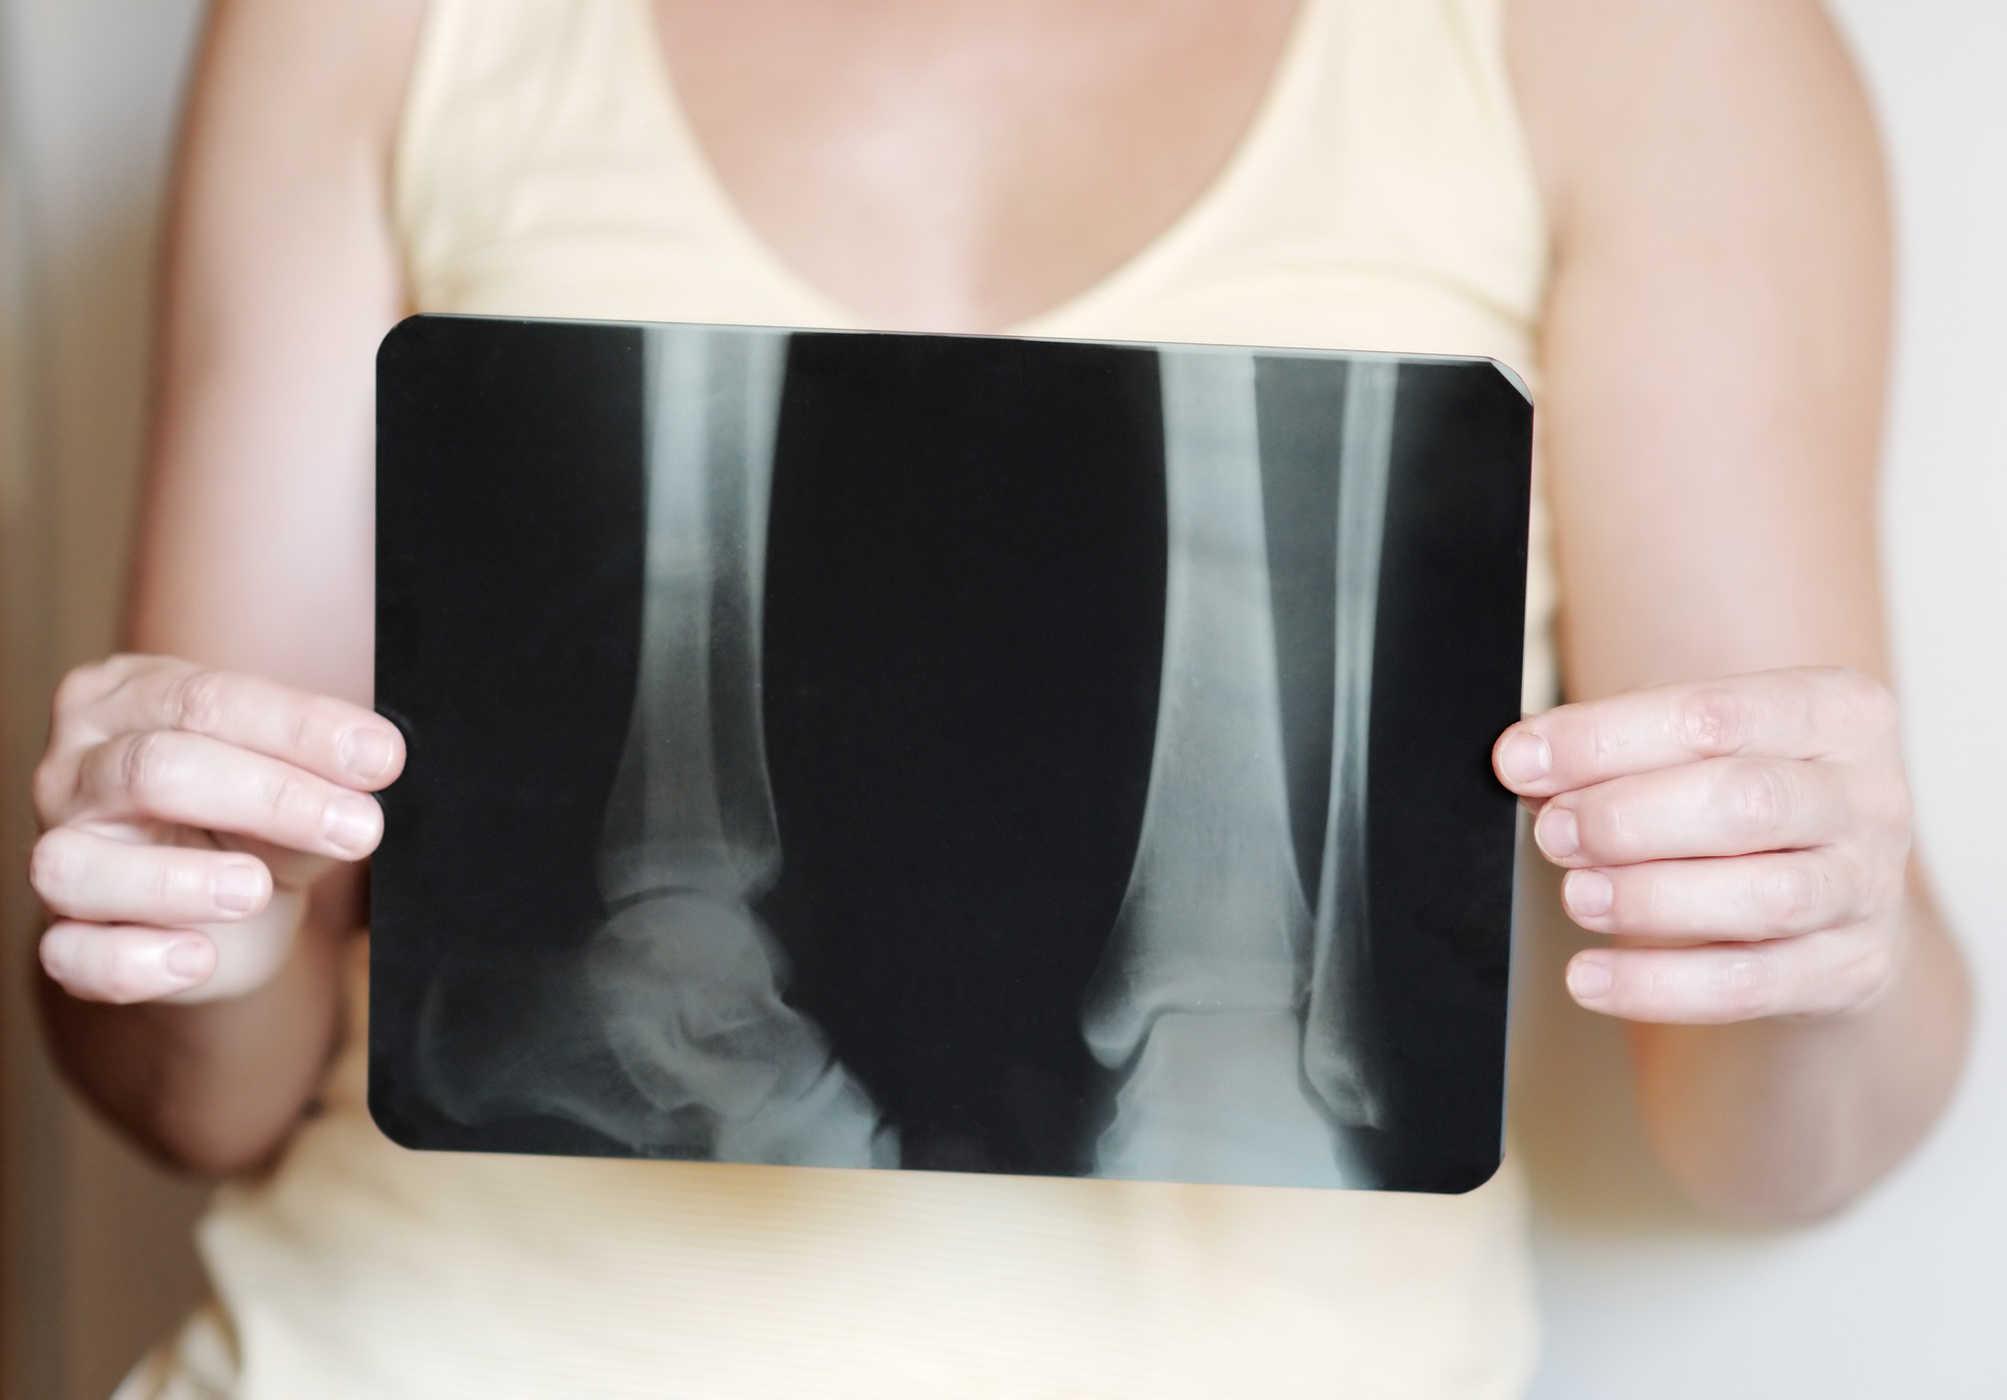

- Loãng xương;

- Để tăng mật độ khoáng xương, bạn uống 50 đến 200 mg mỗi ngày, trong 2 năm;